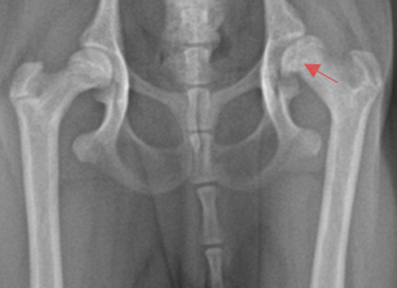

고관절 이형성증(Hip displasia) 및 대퇴골두 무혈성 괴사(LCPD)

고관절 이형성증과 대퇴골두 무혈성 괴사는 반려동물에서 고관절의 비정상적인 형성과 혈액 공급 장애로 인해 심한 통증과 운동 장애를 일으키는 질환입니다. 본원에서는 정확한 진단과 함께 대퇴골두 절제술(FHNO) 등 적절한 수술 치료를 통해 통증 완화와 기능 회복을 목표로 합니다.